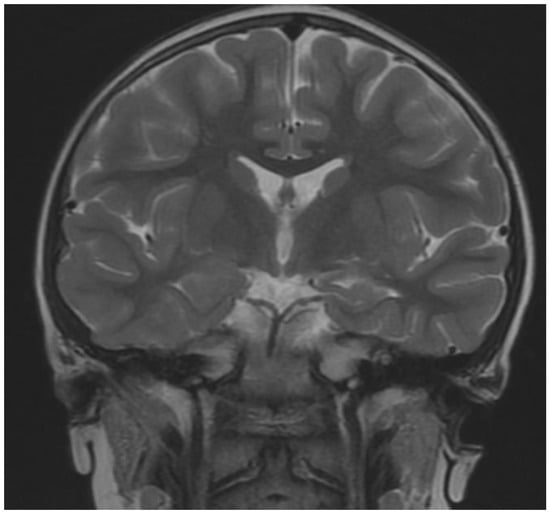

| Brain MRI | |

| yes | Changes in temporal lobe- cyst |